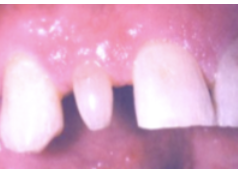

Regional Odontodysplasia

**Ghost Teeth** * occurs in 1 quadrant